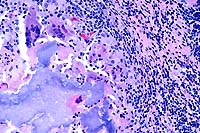

2x

obj.

- Case 23-4. Ureter, perirenal fat. There is a large

granuloma within the periureteral fat which contains a cross

section of a nematode parasite.

- Case 23-4. Parasitic granuloma. Three cross-sections

of a nematode parasite contain profiles of ovaries and multiple

cross-sections of nematode digestive tract.